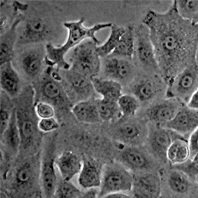

A 549